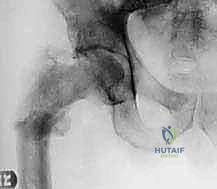

| الأشعة السينية (X-rays) | التقييم الأولي السريع لشكل العظم، اكتشاف الكسور المرضية، وتحديد نمط تدمير العظم. | تعطي الجراح فكرة عامة عن حجم المشكلة وموقعها. |

قبل الغوص في التفاصيل المعقدة للعملية الجراحية، من الضروري جداً أن نؤسس فهماً دقيقاً لتشريح عظم الفخذ (Femur). يُعد عظم الفخذ أطول وأقوى وأثقل عظم في الهيكل العظمي للإنسان. إن الفهم العميق لتشريحه، وخاصة مناطق الفخذ القريبة (Proximal - الجزء العلوي القريب من الحوض) والوسطى (Diaphysis - الجذع)، أمر بالغ الأهمية لكل من الجراح والمريض. تُعد هذه المناطق، للأسف، مواقع مفضلة وشائعة لنمو الأورام العظمية الأولية (السرطانات التي تنشأ من خلايا العظم نفسه مثل الساركوما العظمية Osteosarcoma) والأورام النقيلية (Metastatic Tumors - السرطانات التي تنتشر إلى العظم من أعضاء أخرى مثل الثدي، البروستاتا، أو الرئة).

1. الجزء العلوي من عظم الفخذ ومفصل الورك (Proximal Femur)

الجزء العلوي من عظم الفخذ هو تحفة من الهندسة الحيوية، مصمم لتحمل أوزان هائلة وتوفير نطاق حركة واسع. يشمل هذا الجزء: رأس الفخذ (Femoral Head)، عنق الفخذ (Femoral Neck)، والمدورين الكبير والصغير (Greater and Lesser Trochanters). هذه المكونات تتداخل مع عظم الحوض لتشكيل مفصل الورك (Hip Joint).